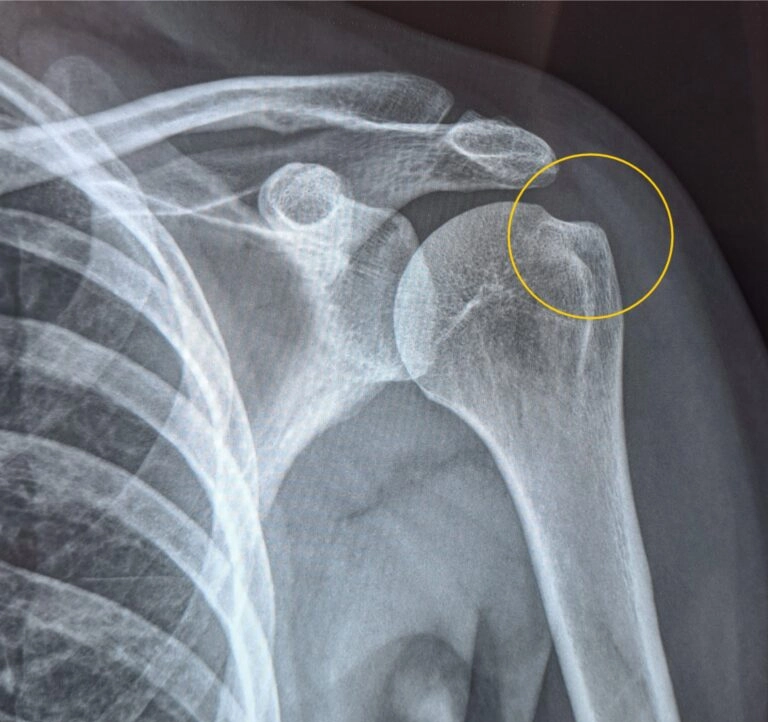

Bolečine v rami

V naši kliniki učinkovito in dolgoročno odpravljamo bolečine v rami, ki so posledica naslednjih stanj ramenskega obroča.

• Kalcinirajoči tendinitis rame

• Adhezivni kapsulitis

• Burzitis rame

• Izpah rame

• Sindrom rotatorne manšete

• Artroza ramena

• Ruptura tetive supraspinatusa

• Popolna ruptura tetive supraspinatusa